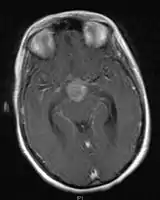

- Mainly located in midline structures, suprasellar region or pineal gland, also basal ganglia and hypothalamus

- Pineal Gland Germinoma

- Suprasellar Germinoma

- Toronto; 2006 (1995-2004) PMID 16530340 -- "Limited-field radiation for bifocal germinoma." (Lafay-Cousin L, Int J Radiat Oncol Biol Phys. 2006 Jun 1;65(2):486-92.)

- Retrospective. 6 patients with bifocal germinoma (pineal + suprasellar). All with diabetes insipidus at presentation. Treated with chemo followed by limited-field RT (whole ventricle 24-40 Gy +/- boost). Median F/U 4 years